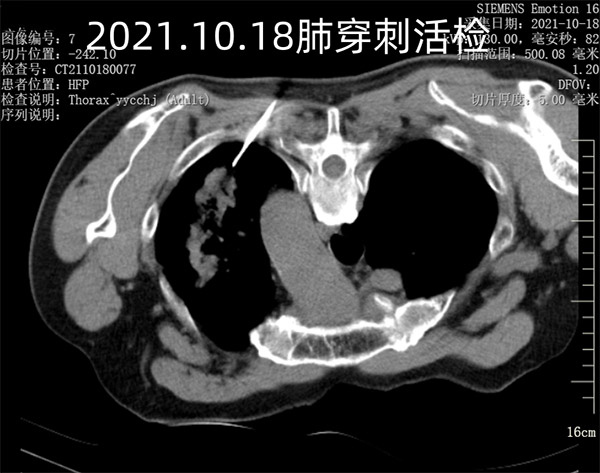

81岁的刘大爷,2021年体检时发现左肺占位病变。家属出于对老人年龄的担忧,及对手术的恐惧,询问了多家医院后,拒绝了配合明确诊断的各项诊疗方法。通过朋友介绍,慕名找到了沈阳市第十人民医院(沈阳市胸科医院)介入科张申众主任,张主任了解情况后,耐心细致的给大爷和家属讲解明确诊断的重要性,还画图说明活检的位置,通过有效的沟通,刘大爷同意配合治疗。为了确保手术的安全性及有效性,经过一系列术前的检查及缜密的身体状况评估,手术如期进行,一周后穿刺活检确诊为左肺上叶肺癌,双肺转移,纵隔淋巴结转移,心包转移。家属在得到这个明确诊断后,感到无比绝望,晚期肺癌等于对患者宣判死亡,而这时张主任为刘大爷制定了后续靶向药物、及放射性粒子植入等相配合的个性化晚期肺癌治疗方案。